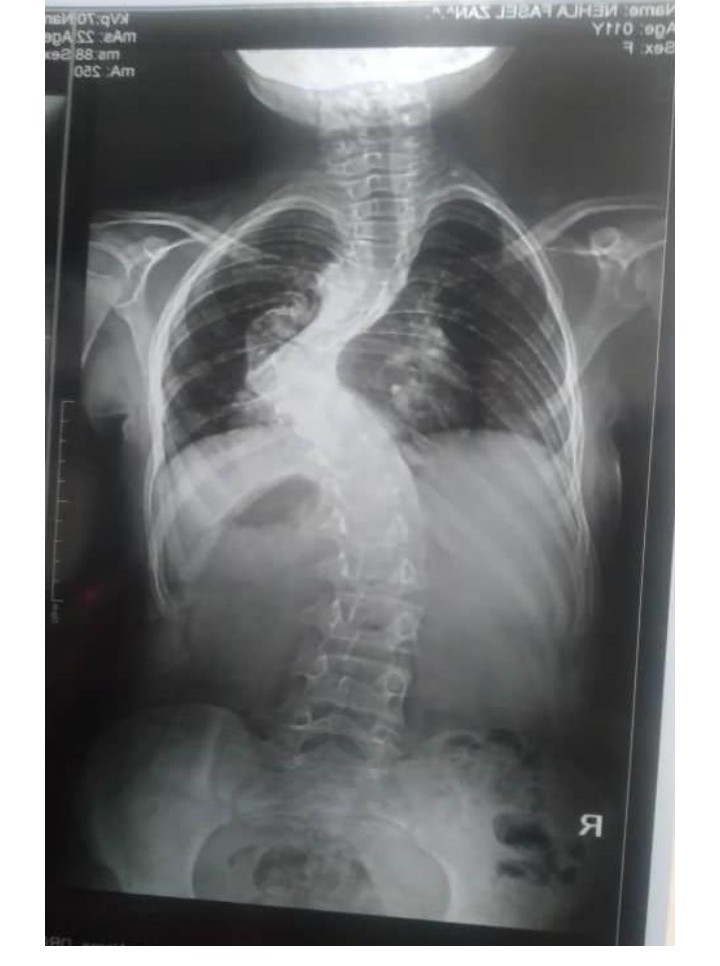

ناشدت الطفلة نهلة المحرمي البالغة من العمر 12 عاماً التي تنتمي إلى جبل محرم في مديرية يافع رصد بمحافظة أبين أهل الخير والعطاء إلى المساهمة في إنقاذ حياتها مما تعاني من تشوه وانحراف شديد في العمود الفقري سبب لها إعاقة وحرمان من العيش حياة طبيعية كبقية الأطفال وهي بحاجة إلى عملية جراحية لتعديل الفقرات في مركز متخصص بالخارج حسب تقرير الأطباء، وبسبب الظروف الصعبة لوالدها لم يتمكن من علاجها في الخارج للتكلفة الكبيرة التي تقدر ب 40 ألف دولار.

ولهذا أطلقت الطفلة نهلة المحرمي مناشدة إنسانية لأهل الخير من أبناء يافع من رجال المال والأعمال وكل المقتدرين المشهود لهم بالفزعات مد يد العون لوالدها لإنقاذ حياتها وعلاجها بالخارج بصورة مستعجلة لأن فقرات عمودها الفقري تزداد بالانحناء والتشوه مع مرور الأيام ما يزيد من تدهور صحتها بصورة مستمرة.